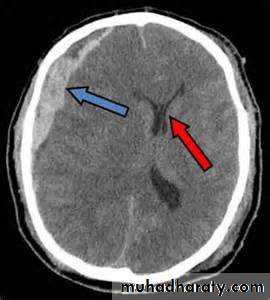

Intracranial hemorrhage

hemorrhage, or bleeding, within the cranial vault [skull] Either within the meninges or parenchymal bleedingtypes

the principle imaging for ICH is CT scanning